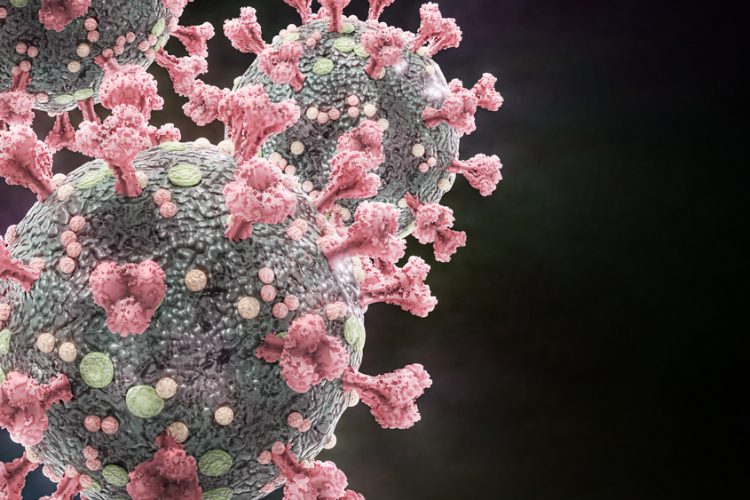

B cell discovery could supercharge future vaccine development

New research reveals how B cells balance mutation and clonal expansion to refine their antibodies. This discovery could lead to more targeted and effective vaccine designs for various diseases.